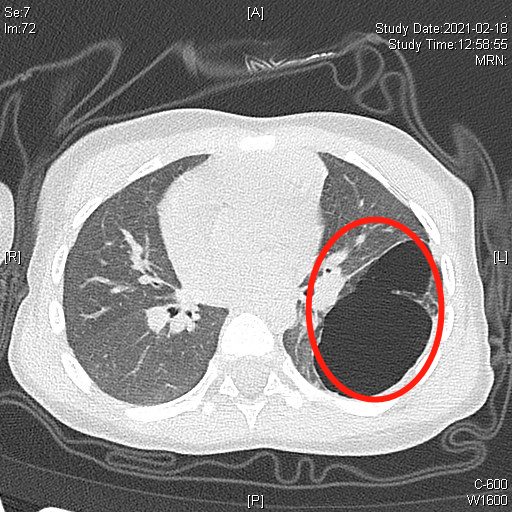

晗晗出生后最初没有明显症状,近期,她突然咳嗽咳痰加剧,在当地医院检查肺部CT发现左肺囊性病灶较刚出生时增大了不少,有3.8×6.4×5.6cm,相当于一个鸡蛋大小。

▲CT显示左侧胸腔巨大病灶